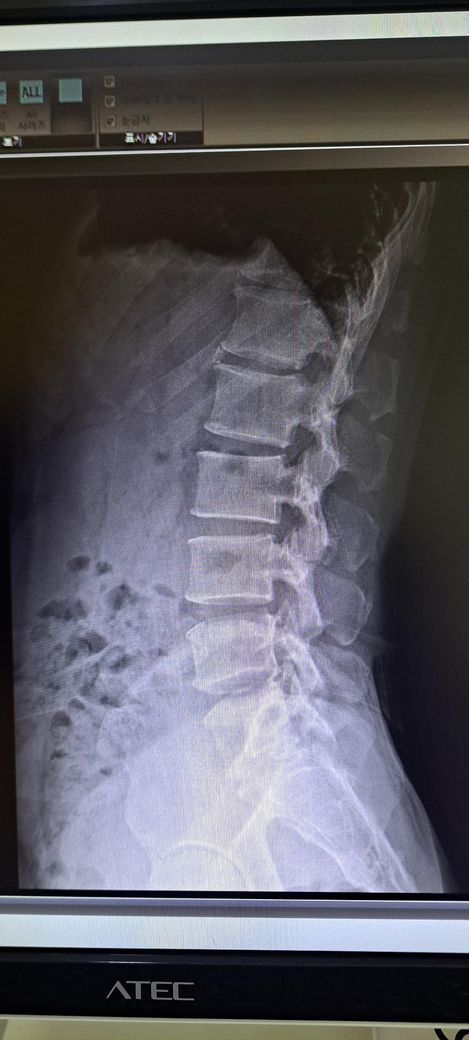

x ray 촬영한 영상인데 골반 틀어짐 및 전방경사 심각한가요? 골반 틀어짐은 어느 쪽을 교정해야 하며 골반 틀어짐 및 전방경사 교정 방법을 알려주시면 감사하겠습니다 .

전방경사 약간 있어 보이나 흔한 범위일 가능성이 크며, 스트레칭.근력운동으로 충분히 교정 가능한 수준으로 보입니다.

일단 골반 같은 경우 좌우 대칭이 다르며 약간의 전방 경사 및 틀어짐이 있는 것으로 보입니다.

허리가 과하게 꺽여 있고 엉덩이는 뒤로 빠져 있는 상태라고 추측되며 측만은 아니라고 생각됩니다.

정면 사진상 골반의 좌우높이 차이가 관찰되며, 이는 대퇴골의 위치변화와 연관되어 보입니다. 측면 사진에서 요추의 곡선이 다소 꺾여 있는 양상이 보여 골반 전방경사 가능성이 큽니다. 정면 영상에서 척추가 일직선이 아니라 완만한 S자 형태로 휘어있는 측만 소견이 보입니다. 심각한 수준은 아니나 지속적인 관리가 필요한 상태입니다. 측면 사진상 경추의 커브를 보면 일자목 상태입니다. 골반이 높은쪽의 근육은 이완시키고, 낮은쪽과 약해진 둔근, 복근을 강화하는 운동이 필요합니다. 전방경사 완화를 위해 장요근 스트레칭과 프랭크 같은 코어 운동이 효과적입니다. 흉쇄유돌근 스트레칭과 더불어 등 근육을 강화하여 어깨를 펴는것이 급선무입니다.

전방경사의 경우 현재 요추는 요추전만이 잘 만들어져있기 때문에 골반의 경사가 문제가 되는 상태가 아닌걸로 판단됩니다.